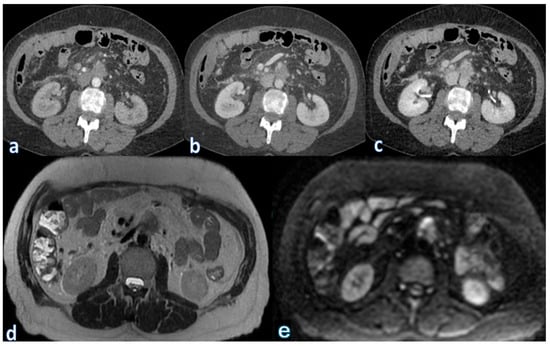

The progression of postoperative fluid collections follows a predictable pattern. Acute fluid accumulations and pancreatic necrosis typically occur within the first week after surgery. By the second to third week, infected necrosis becomes more common, while by the fourth week or later, these collections may transform into pseudocysts or pancreatic abscesses. Identification and characterization of these collections are mostly dependent on cross-sectional imaging, especially contrast-enhanced computed tomography (CECT) and magnetic resonance imaging (MRI).

On CECT, acute fluid collections appear as hypoattenuating areas near the surgical site, often irregular in shape and located adjacent to the pancreatic remnant, anastomotic sites, or nearby vascular structures. In the early stages, these collections are confined by the abdominal fascia and typically lack a discernible capsule.

On MRI, particularly T2-weighted imaging with fat saturation, fluid collections appear hyperintense, though their signal may be inhomogeneous if proteins or hemorrhagic components are present. Hypointense regions within the collection may correspond to blood degradation products, indicating a more complex composition (Figure 2).

In cases of pancreatic necrosis, CECT reveals heterogeneous attenuation due to the presence of nonviable tissue, fat, and hemorrhagic debris [128]. On T2-weighted MRI, necrotic regions appear inhomogeneous, reflecting the mixed composition of necrotic debris and surrounding inflammatory changes. Pancreatic necrosis is often partially or completely encapsulated, forming a well-defined peripheral rim with contrast enhancement on both CT and MRI, suggesting organizing necrosis or early wall formation [73,129]. If the necrotic collection becomes superinfected, the presence of air bubbles within the collection becomes a key diagnostic feature. On CT, air bubbles appear as low-density foci, while on MRI, air appears as signal voids across all sequences, confirming the presence of infection.

Pseudocyst development and pancreatic abscesses are examples of late consequences. On both CT and MRI, pancreatic abscesses appear as fluid collections with a thicker, enhancing wall. The diagnosis is confirmed by the presence of intralesional air, which is pathognomonic for infection. Conversely, pseudocysts are spherical, well-circumscribed fluid collections that seem uniformly hypoattenuating on CT. They are easy to distinguish from solid or necrotic lesions on MRI because they appear hypointense on T1-weighted imaging and uniformly hyperintense on T2-weighted imaging. Debris from the pseudocyst can occasionally be seen at the bottom of the sample as hypointense, irregular material.